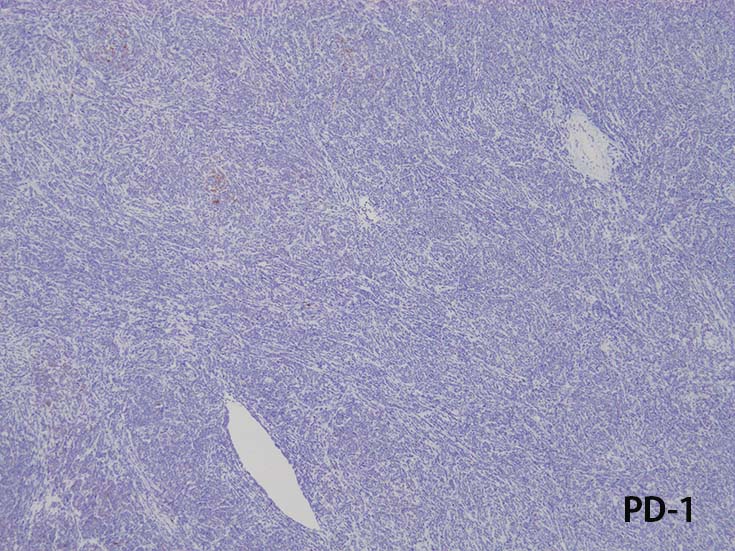

- CD1a, CD2, surface CD3 (dim), CD4, CD5, CD8は種々の程度に発現する.

- T-ALL はしばしば, CD4とCD8の double positive となる. またCD10が陽性になる

- CD4,CD8 double positiveはT-prolymphocytic leukaemiaでも認められる. CD10もPTCL(第一にはAITL)に陽性となることに注意.

- cytoplasmic CD3 のみがT-cell lineage特異的なマーカである.